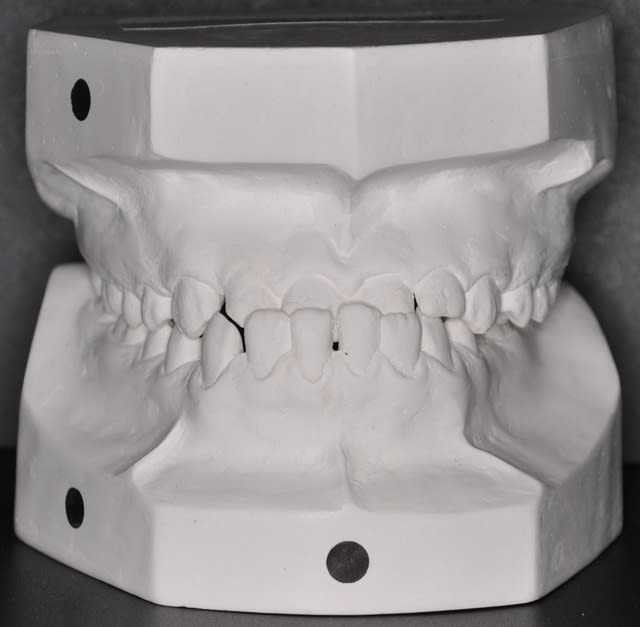

les dernieres photos du cas

- La 4ème photo n'est pas exacte, ton patient à latéroglissé à gauche. Tu l'as prise comme ça volontairement ?

**non, c’est une photo avec miroir qui montre bien les rapport molaires et canines et qui montre le début de la correction de l’articulé en jouant sur le sens transversal de l’arc niti

Saïd, je pense que nous devons faire confiance à Takamatika. C'est lui (elle ?) qui a fait l'examen clinique et positionné les modèles en plâtre.

oui mais Takamatika a mis les modèle en PIM et Saïd voudrait les voir en RC. Quel est le chemin de fermeture?